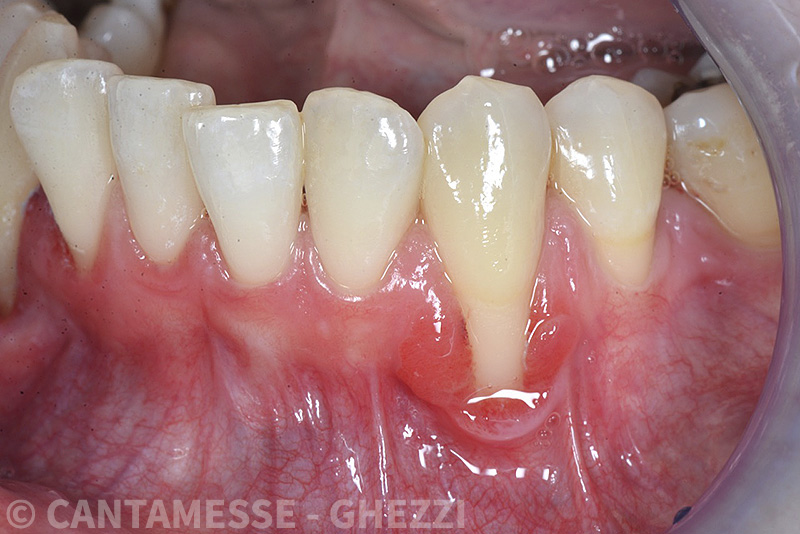

PREMESSA: in seguito all’estrazione dell’incisivo laterale superiore di destra, resasi necessaria per cause batteriche, si decide di affrontare il caso con il posizionamento di un impianto in sostituzione dell’elemento mancante dopo guarigione del sito infetto. Con tecniche rigenerative sia dei tessuti ossei mancanti a causa dell’infezione pregressa, sia dei tessuti gengivali che appaiono inizialmente troppo spostati in alto, si ripristina una corretta morfologia delle parabole (contorni) gengivali e delle papille interdentali (triangoli di gengiva tra due denti vicini).